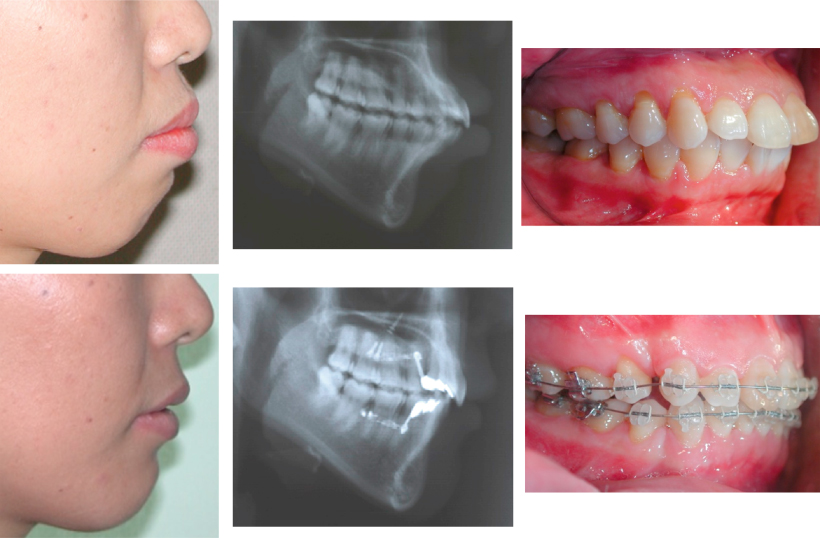

Severe protrusion of the upper teeth treated WITHOUT Headgear, Forsus Mouth Protrusion Braces Treatment almost always involves using braces to straighten crooked, crowded or protruding teeth, close gaps between teeth, and correct the bite. Invisalign is also one of the orthodontic. Open bite malocclusion, or protruding teeth, is one of the most challenging dental problems to treat. Whether with braces, or clear aligners like invisalign/ invisalign® teen or 3m clarity aligners™, you’ll be. Mouth Protrusion Braces.

ORTHODONTICS Bimaxillary Protrusion Treated with Insignia® System Mouth Protrusion Braces If your child has protruding front teeth, there could be several reasons for it. Buck teeth, or protruding front teeth, describe a type of bite issue where the top row of teeth overlaps with the bottom row. Whether with braces, or clear aligners like invisalign/ invisalign® teen or 3m clarity aligners™, you’ll be glad to know that we can fix.. Mouth Protrusion Braces.

4 First Premolar Extraction for Bimaxillary Protrusion Dental Braces Mouth Protrusion Braces How to fix protruding teeth without braces. Invisalign is also one of the orthodontic. Yes, orthodontic treatment with different types of braces can fix protruding teeth. This condition may be inherited, or it could be caused by an. Prognathism is a protrusion of your upper jaw, lower jaw or both. If your child has protruding front teeth, there could be. Mouth Protrusion Braces.

Comprehensive orthodontic treatment with extraction of 4️⃣ premolars Mouth Protrusion Braces How to fix protruding teeth without braces. Invisalign is also one of the orthodontic. Prognathism is a protrusion of your upper jaw, lower jaw or both. What causes protruding top teeth? Yes, orthodontic treatment with different types of braces can fix protruding teeth. Open bite malocclusion, or protruding teeth, is one of the most challenging dental problems to treat. Buck. Mouth Protrusion Braces.

Correction of severe bimaxillary protrusion with first premolar Mouth Protrusion Braces Whether with braces, or clear aligners like invisalign/ invisalign® teen or 3m clarity aligners™, you’ll be glad to know that we can fix. How to fix protruding teeth without braces. What causes protruding top teeth? Prognathism is a protrusion of your upper jaw, lower jaw or both. Treatment almost always involves using braces to straighten crooked, crowded or protruding teeth,. Mouth Protrusion Braces.